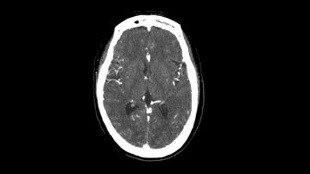

Nöroloji Görüntü Galerisi